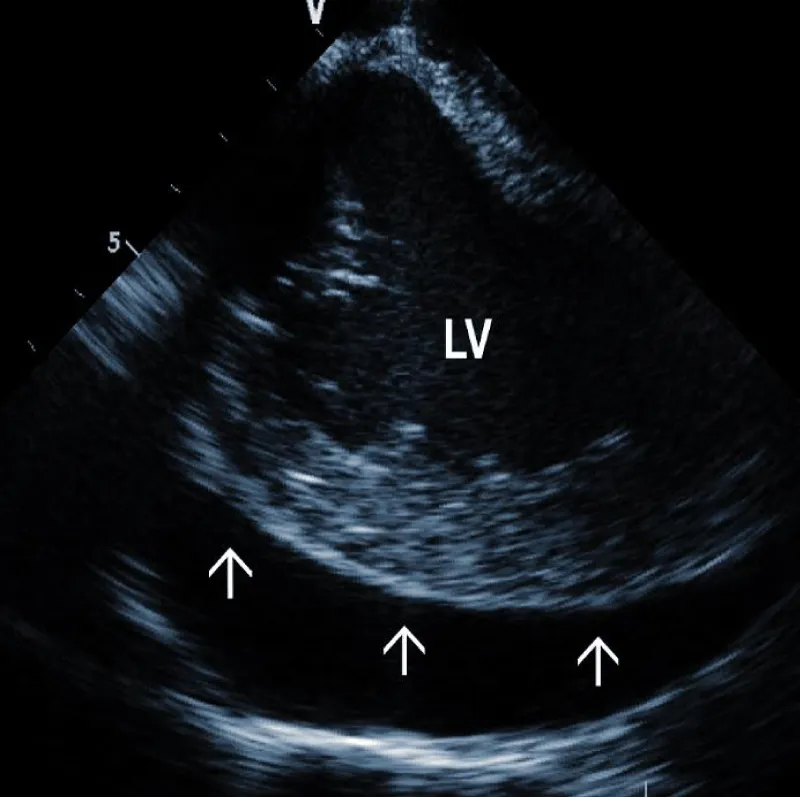

Technically speaking, the presence and size of intracardiac masses in patients suspected of infective endocarditis are critical in planning TLE procedure (Figure 2B). Large vegetations were found more common in patients with renal failure, heart failure, ICD system, and loops of the leads [14]. In another study, diabetes was related to larger vegetations, similarly younger age. Anticoagulation therapy resulted in smaller vegetations [15].

Figure 2B: Large vegetation floating on the ICD lead in the Right Atrium (RA). RV: Right Ventricle.

In patients with a definite diagnosis of lead-related infective endocarditis, the size of vegetations may determine the strategy of lead removal. Smaller vegetations ­< 3 cm can be extracted transvenously, while larger vegetations often require surgery. Alternatively, they may be preferably extracted by a vacuum-assisted system, usually during the same TLE procedure [16]. Some authors recommended the extraction of large vegetation placement of a Dormia basket under ICE guidance into the pulmonary artery to capture embolic material [17].